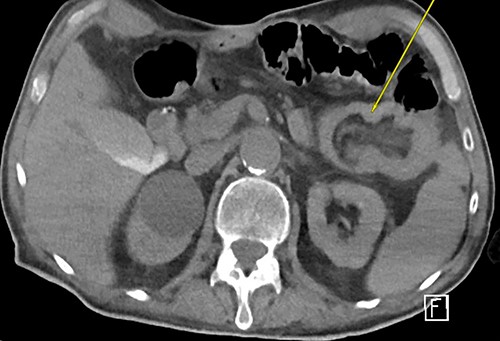

The patient underwent an exploratory laparotomy identifying the segment of intussusception in the jejunum (Fig. 3). The segment was resected (Fig. 4) and a new JT was placed. The patient was discharged successfully 8 days later. Final pathology revealed findings consistent with intussusception.

Intraoperative findings of jejunojejunal intussusception with distal collapsed bowel (white arrow) and proximal dilated bowel (black arrow).